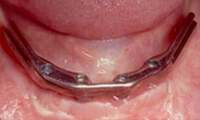

틀니 안쪽에 작은 고정장치가 있어

단추처럼 임플란트에 ‘딸깍’하고 끼워지는 구조라

일반 틀니보다 훨씬 덜 흔들리고 안정감이 좋습니다.